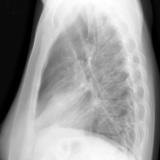

Case 2 Lateral

Date: 02/28/2004

Views: 3380